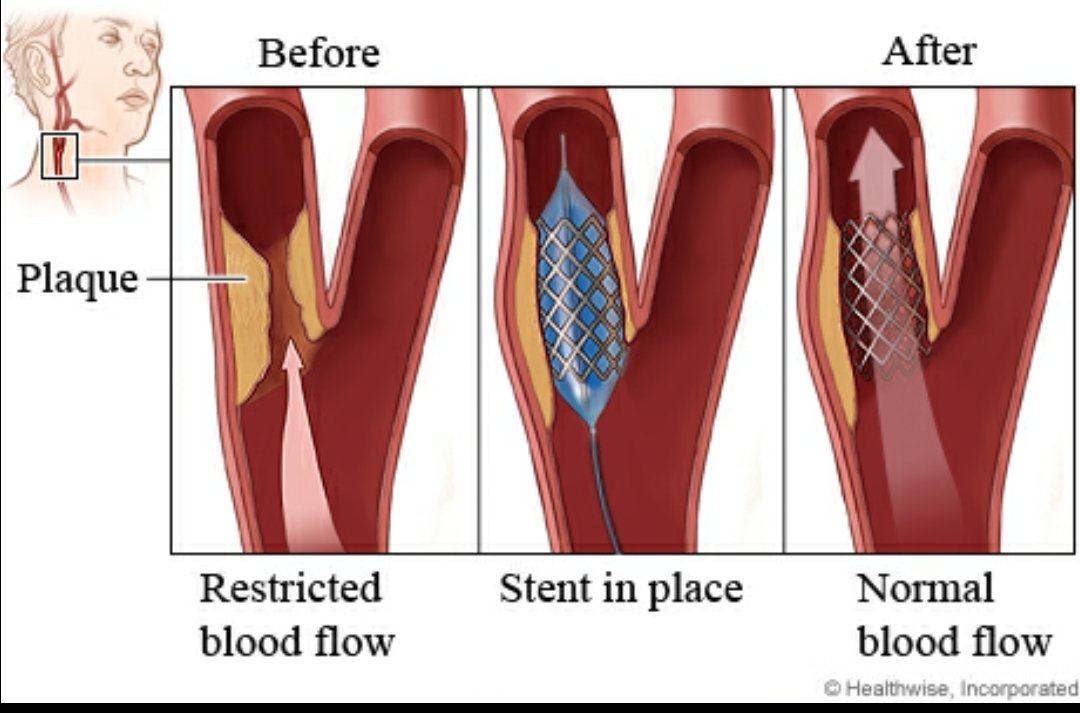

♦️عمل دعامات حال وجود تضيق في الشرايين

♦️عمل دعامات حال وجود تضيق في الشرايين

🧠عملية القسطرة التي يمكن إجراءها

♦️اول ٦ ساعات♦️من ظهور الأعراض

🧠عملية القسطرة التي يمكن إجراءها

♦️اول ٦ ساعات♦️من ظهور الأعراض